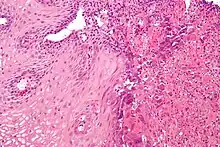

![]() | |

| An esophageal ulcer visualized by esophagoscopy: the reddened area at 10 o'clock on the surface of the mucosa. | |